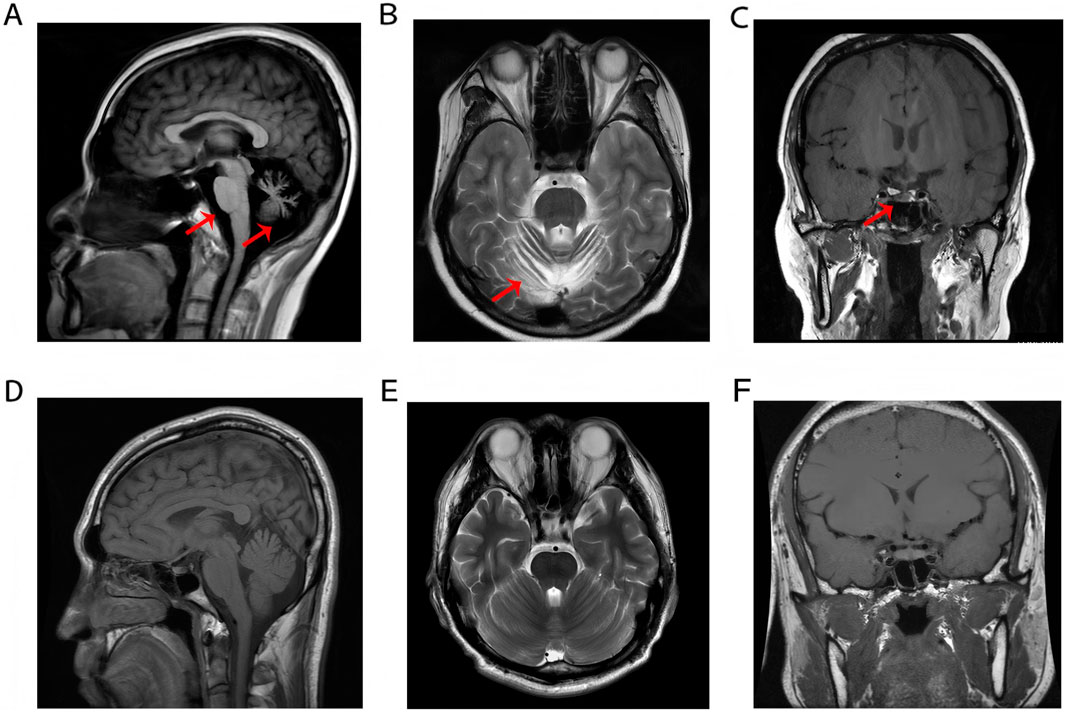

Brain Magnetic Resonance Imaging (MRI) revealed cerebellar atrophy with mild thinning of the pons and medulla oblongata (Figures 1A,B). Coronal MRI reveals atrophy of the anterior pituitary lobe, revealing diffuse volume loss and symmetric thinning to a height of 1–2 mm, and an anatomically normal posterior pituitary and stalk (Figure 1C). These features were compared with normal control MRIs (Figures 1D–F). Fundoscopic examination revealed pale optic discs with blurred margins, tortuous retinal arteries and veins, extensive atrophy of the posterior pole, and peripheral retinal depigmentation with pigmentary changes. The macular foveal reflex was absent. Optical coherence tomography (OCT) of both eyes demonstrated thinning and atrophy of the macular retina (Supplementary Figure S1). The hormone profile of the pituitary-thyroid axis revealed a markedly suppressed thyroid-stimulating hormone (TSH) level of <0.005 mIU/L, elevated free triiodothyronine (FT3) at 11.37 pmol/L, elevated free thyroxine (FT4) at 36.25 pmol/L, and a thyrotropin receptor antibody (TRAb) level of 5.97 IU/L. These findings collectively indicated thyrotoxicosis. Hormonal assessment of the pituitary-gonadal axis revealed decreased levels of testosterone (TES), luteinizing hormone (LH), follicle-stimulating hormone (FSH), and androstenedione (AND) establishing the diagnosis of hypogonadotropic hypogonadism.

FIGURE 1

(A–C) Cerebellar atrophy with brainstem thinning and anterior pituitary atrophy. (D–F) Normal MRI demonstrates preserved anatomical morphology and homogeneous signal intensity of the pons, medulla oblongata, cerebellum, and pituitary gland in a healthy control subject.